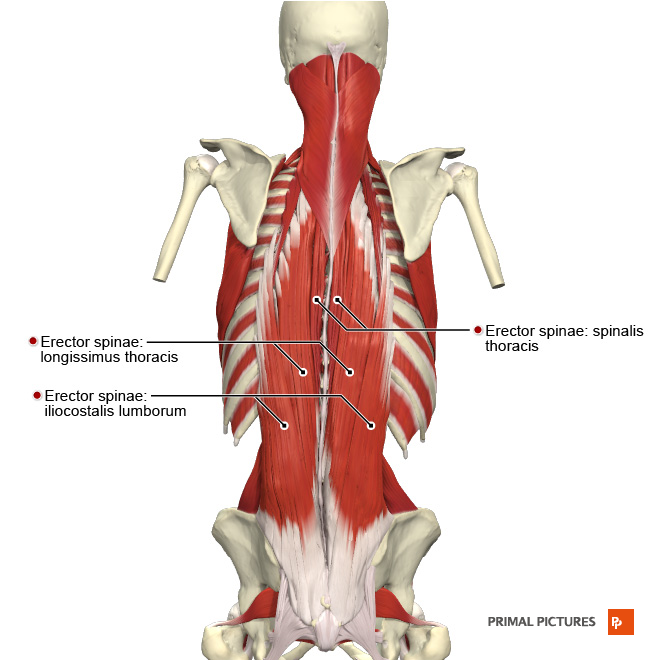

Back muscle

1. Superficial Group |

Scapula movement - Trapezius (승모근) - Latissimus Dorsi (광배근) - Levator Scapulae (견갑거근) - Rhomboid major (대능형근) - Rhomboid minor (소능형근) |

2. Intermediate Group  |

Rib movement - Serratus posterior superior (상후거근) - Serratus posterior inferior (하후거근) |

3. Deep(Intrinsic) Group |

Neck & Head movement - Splenius Capitis (두판상근) - Splenius Cervicis (경판상근) Erector spine - Iliocostalis (장늑근) - Longissimus (최장근) - Spinalis (극근) Transversospinales - Semispinalis (반극근) - Multifidus (다열근) - Rotatores (회전근) |